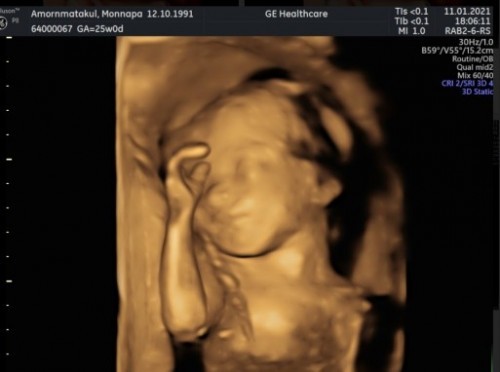

19วีค2วัน อยากรู้แล้วว่า ผู้หญิงหรือผู้ชาย แม่ๆได้กี่วีคกันแล้ว รู้เพศกันยังคะ ❤️